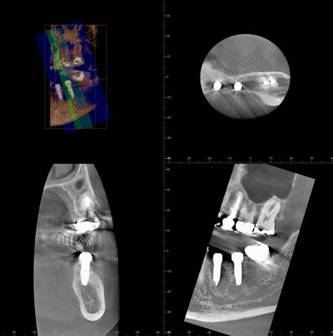

術後のCBCT

インプラントの重大な事故は下顎管から十分な距離をとれば防げます

抜歯部位にインプラントを追加しました。CBCT